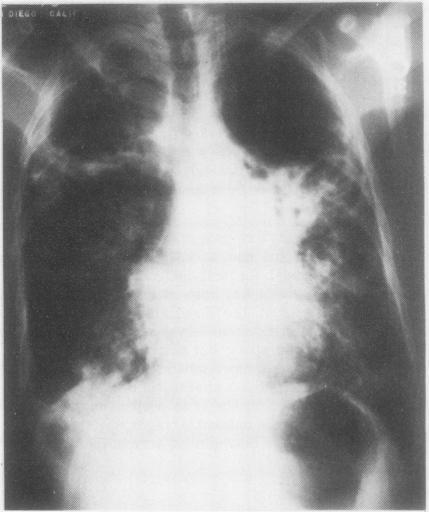

Large cavitary dead space as an unusual cause of hypercapnic respiratory failure in pulmonary tuberculosis.

https://cdn.ncbi.nlm.nih.gov/pmc/blobs/0631/459369/2a3068a26c1d/thorax00199-0070-a.jpg